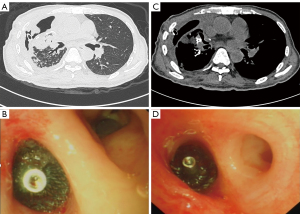

The chest computed tomography (CT) suggested right-sided hydro-pneumothorax and pneumonia (Figure 1A). The pleural effusion examined by metagenomic next generation sequencing (mNGS) revealed the presence of M. chelonae. He was therefore treated with sensitive antibiotics (amikacin plus ciprofloxacin), chest drainage, transbronchoscopic closure with 2 mL biological glue (Beijing Kangpaite Medical Equipment Co., Ltd., Beijing, China), and oxygen supplement. However, the pneumothorax and empyema did not resolve successfully. Due to his poor pulmonary function and deficient nutritional state, bronchoscopic one-way endobronchial valve (EBV) implantation was adopted as an ideal modality. First, the right upper lobe (RUL) was suspected as the target lobe as blue liquid flowed out from the RUL after instilling 20 mL methylene blue solution through the thoracic catheter. Second, under negative thoracic pressure drainage (−10 cmH2O), the Chartis air leak monitoring system (American Pulmonx Inc) visually displayed an intense negative pressure, indicating that the B2 and B3 segments of the RUL had effective communication to the leak when the catheter tip was exposed to the fistula, with no bypass ventilation (Figure 1B). After measuring the bronchial lumen, we decided to implant two Zephyr EBVs (Emphasys Medical Inc, USA) at the opening of B2b (EBV-TS-5.5) and B3b (EBV-TS-4.0), respectively (Figure 1C,1D). The amount of air leak was reduced by approximately 50% by visual inspection of air bubbles in the water seal, and the Chartis system showed a typical decreasing breathing curve. No adverse events occurred after the procedure. However, due to the right empyema, the patient required repeated pleural lavage with sodium chloride solution through the chest tube. The air leakage finally resolved on September 22, 2018, and the chest tube was removed after three days. The patient was able to conduct daily activities after discharge. The whole process of diagnosis and treatment of BPF related to M. chelonae was outlined in Figure 2.